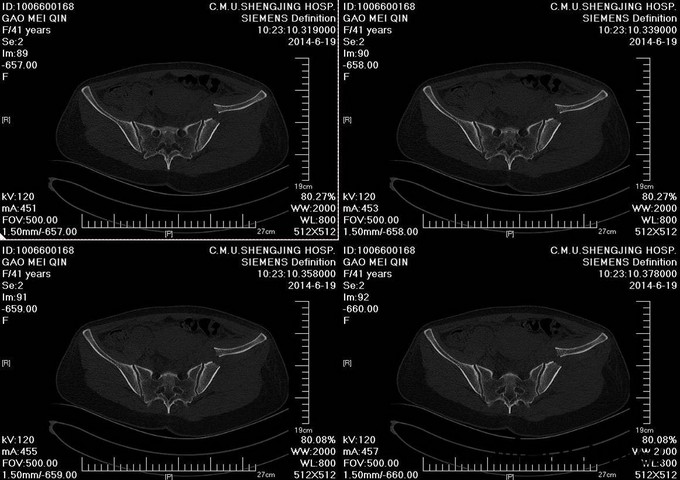

主诉:车祸外伤后左髋部疼痛伴活动受限4天 患者于2014年6月12日早6点左右被皮卡车撞伤,伤后患者出现一过性昏迷,被急诊送往当地医院,行DR及CT检查后,诊断为:左髋臼骨折,于当地医院骨科行骨牵引、抗炎补液等对症治疗后,现为求进一步治疗转入我科,患者病来无头晕头痛,无恶心呕吐,已排气排便.

患者左下肢股骨髁上骨牵引中,左髋部肿胀,臀部可见淤血瘀斑,骨盆分离挤压试验(+),左大腿肿胀,左下肢无明显短缩,纵向叩击痛(+),左下肢小腿外侧及足背麻木感,足背伸肌力正常,双足趾可活动,双侧足背动脉可触及搏动